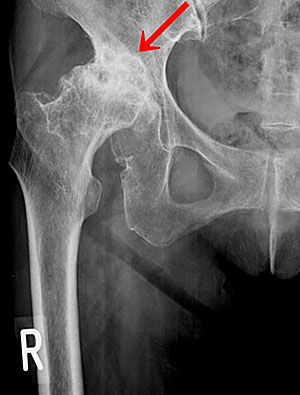

全人工股関節置換術

手術前